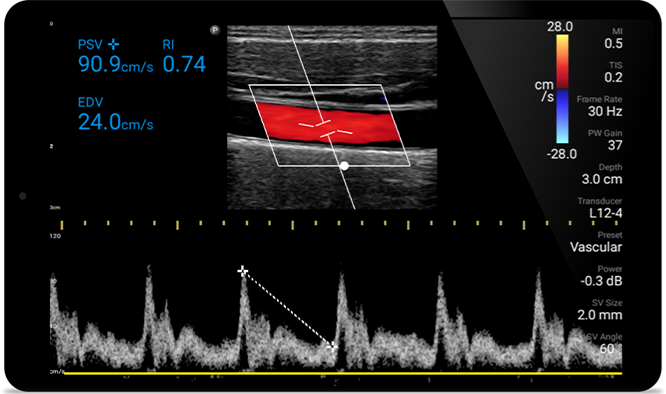

La insuficiencia cardíaca congestiva es un problema creciente en la actualidad. Su detección temprana a través de un ultrasonido en el consultorio puede mejorar en gran medida las tasas de supervivencia.

Evaluación de la función ventricular izquierda